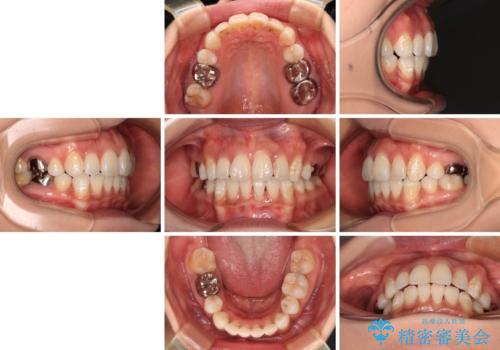

ワイヤー装置の抜歯矯正で横顔の口元の印象をすっきりと

- 口元の閉じにくさを気にして来院された患者様です。

上下ともに歯列が前方に突出していたため、上下左右の第一小臼歯4本を抜去し、ワイヤー装置による矯正治療を行うこととしました。

舌の突出癖による影響もあったため、舌のトレーニングを並行して実施しました。

左下奥歯にむし歯が認められるため、矯正治療後にセラミックインレーにて修復治療を行うこととしました。

4本の歯を抜歯したことで、飛び出していた口元が引っ込み、横顔が大きく改善されました。